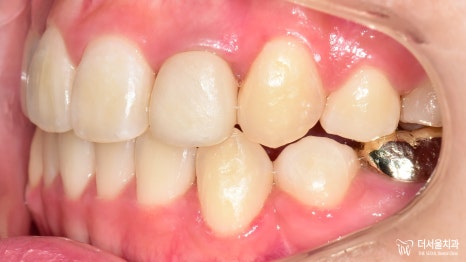

구내 사진을 보면

삐뚤빼뚤 했던 치열들이

제 위치를 찾아가 있는 모습입니다.

정중선도 잘 맞고

이전에 크라운을 올려드렸던

22번도 잘 어우러지고 있네요.

스마일라인 또한 자연스럽고

예쁘게 개선되었습니다!